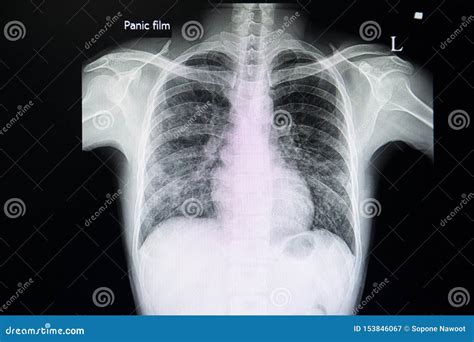

A Pneumonia X-ray is a medical imaging test that uses electromagnetic radiation to create pictures of the inside of your chest. When you have pneumonia, the air sacs (alveoli) in your lungs can become filled with fluid or pus. In an X-ray image, these filled air sacs appear as opaque, whitish patches or "opacities," which stand out against the dark, air-filled healthy lung tissue. This visual evidence is critical for doctors to distinguish pneumonia from other conditions like bronchitis or asthma.

• Determining Severity: It helps the physician understand if the infection is limited to one lobe (lobar pneumonia) or spread throughout both lungs (bronchopneumonia).

When a radiologist reviews a Pneumonia X-ray, they are looking for specific indicators of disease. Healthy lungs on an X-ray typically appear black because they are filled with air, which does not block the X-ray beams. Conversely, infected tissue blocks these beams, leading to white areas on the film. These findings are often referred to in clinical reports as "infiltrates" or "consolidation."

Localized white patches (Consolidation) Indicative of active pneumonia infection

Cloudy shadows Possible interstitial inflammation or fluid

Blunted costophrenic angles Potential sign of pleural effusion (complication)